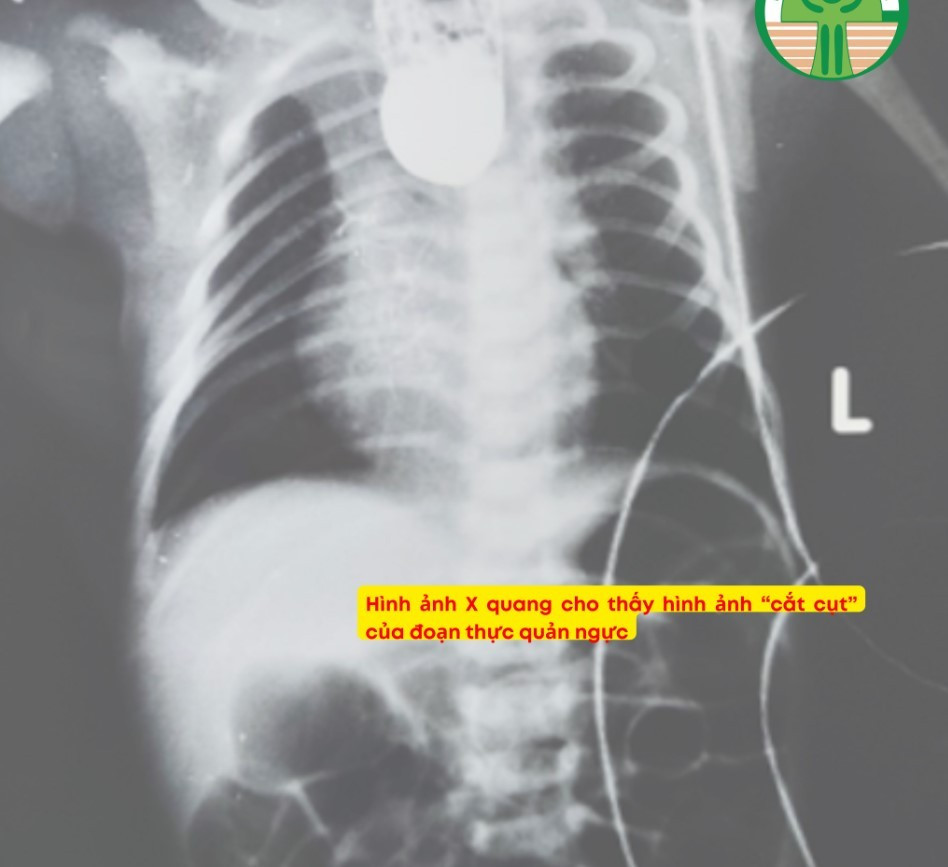

Bác sĩ Chiều cho biết, bệnh nhi là bé trai, sinh mổ ở 37 tuần tuổi thai, cân nặng lúc sinh 2,5 kg. Sau sinh, bé không thể bú sữa, xuất hiện tình trạng sùi bọt cua qua miệng, đặt thông dạ dày thấy vướng. Kết quả chụp X-quang cho thấy thực quản bị gián đoạn, với hình ảnh “cắt cụt” ở đoạn thực quản ngực.